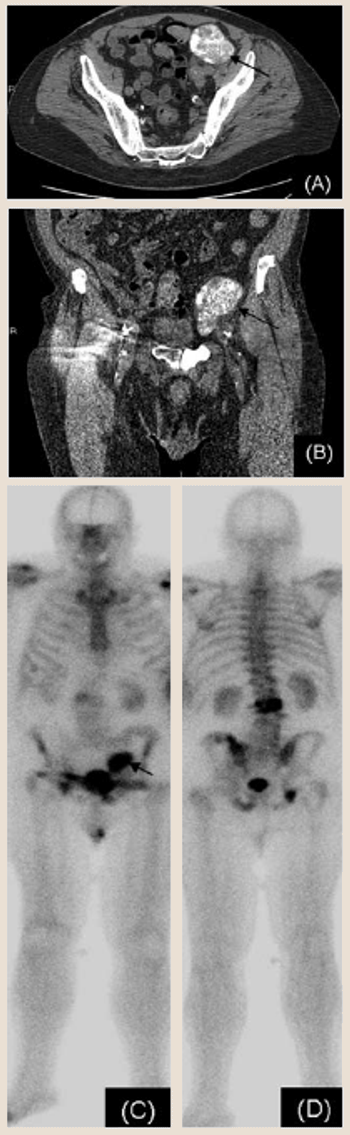

A 79-year-old man was diagnosed with prostate cancer in 1993 after a transurethral resection of the prostate (TURP). The patient had a Gleason score of 5 and was initially treated with low-dose-rate radioactive seed implants.